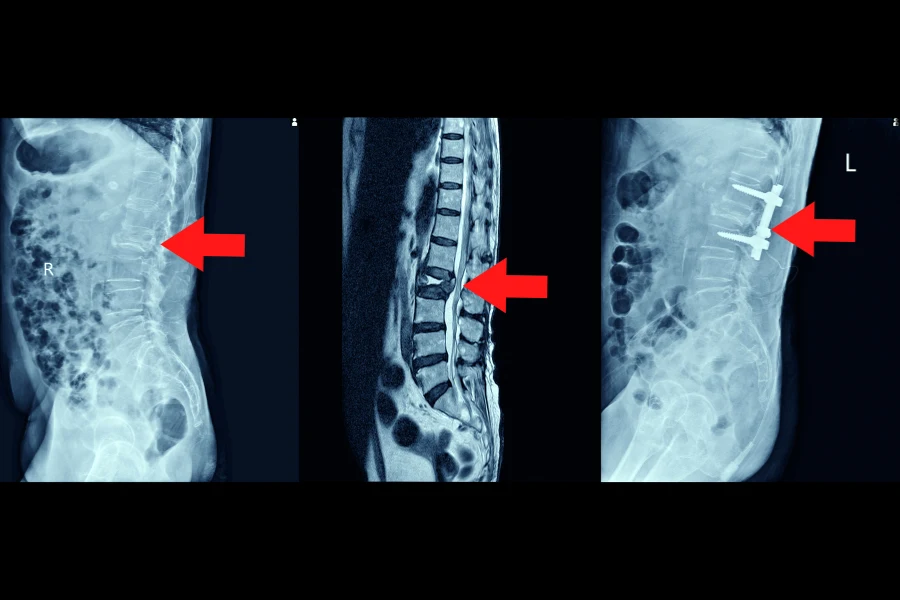

Операція при стенозі показана при виражених неврологічних порушеннях або неефективності консервативної терапії. Основна мета операції на хребті — декомпресія, тобто усунення тиску на спинний мозок чи нервові корінці. Сучасні хірургічні методики дозволяють виконувати втручання максимально безпечно та з мінімальним ризиком ускладнень.

Найпоширенішим методом є ламінектомія або мікродекомпресія, при якій нейрохірург видаляє частину кісткових структур або зв’язок, що стискають нерви. Це дозволяє відновити нормальний просвіт каналу, покращити кровообіг і знизити ризик подальших уражень. При локалізованих ураженнях застосовується мінімально інвазивна хірургія, що прискорює відновлення та зменшує больовий синдром після операції.

У ситуаціях, коли хребет стає нестабільним або коли необхідно зберегти правильне положення хребців, виконується фіксація — стабілізуюче втручання, що передбачає встановлення спеціальних систем із металевих конструкцій. Це допомагає уникнути повторного звуження та забезпечити правильну підтримку хребта під час відновлення. Фіксація може поєднуватися з декомпресією, якщо цього потребує клінічна ситуація.